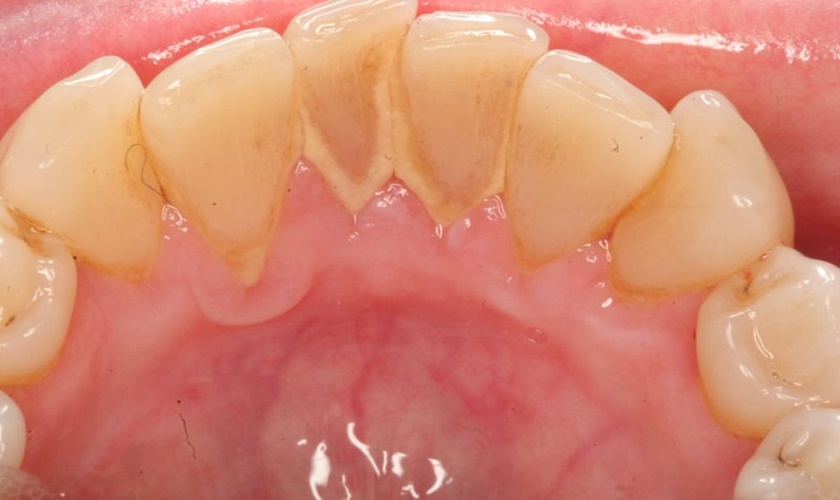

Tiến sĩ, Bác sĩ Võ Văn Nhân, Giám đốc nha khoa Nhân Tâm cho biết: Vôi răng hay còn được gọi là cao răng. Đây là những mảng bám, vụn thức ăn dư thừa còn dính ở chân và nướu răng. Theo thời gian, các mảng bám này sẽ bị vôi hóa và trở nên cứng hơn.

Đánh răng và súc miệng thông thường sẽ không thể loại bỏ được chúng. Thay vào đó, cần phải nhờ tới sự can thiệp của các dụng cụ nha khoa chuyên dụng thì mới có thể làm sạch được các mảng bám này và trả lại sự trắng sáng cho răng.

Vôi răng bám tụ lâu ngày sẽ gây hôi miệng và nhiều bệnh nguy hiểm khác

Bác sĩ Nhân khuyến cáo, ngoài việc đánh răng mỗi ngày thì cạo vôi răng định kỳ tại nha khoa cũng là cách mà mỗi người cần thực hiện. Bởi nếu để tích tụ lâu này, vôi răng sẽ gây nên các bệnh lý như hôi miệng, chảy máu nướu, sưng nướu, viêm nha chu cùng nhiều bệnh về họng khác.